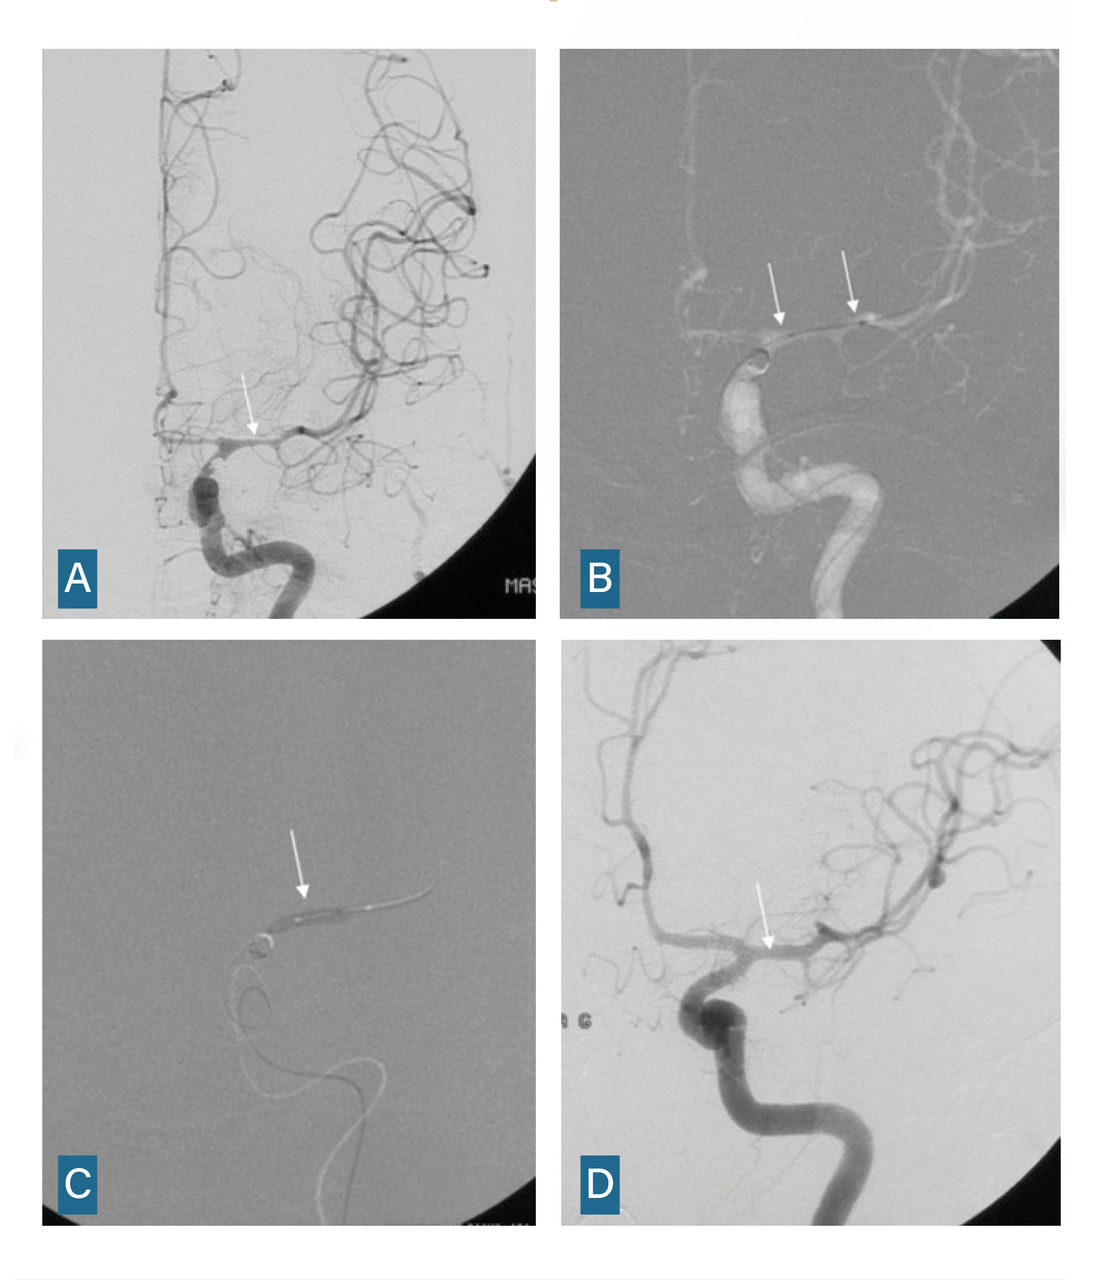

L’angiographie digitale permet de planifier et de suivre le traitement lorsqu’il est réalisé par voie endovasculaire. (fig. 4)

L’imagerie cérébrale intervient également dans le suivi et la prise en charge des complications tardives. En cas de vasospasme résistant au traitement ­médical optimal, une procédure endo­vasculaire est menée, incluant une dilatation chimique et éventuellement mécanique (fig. 5).